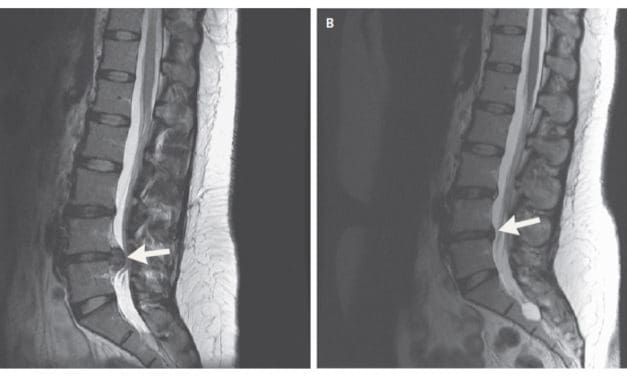

Thérapies manuelles et lombalgie : stop ou encore ?

Éduquer avant d’opérer ?